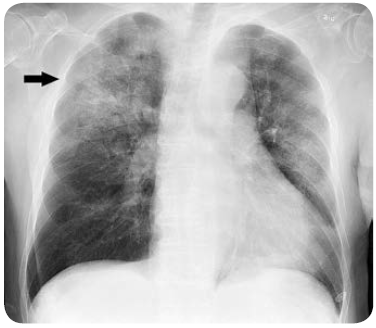

● X-ray : 필요에 따라 기관지염이나 폐렴, 결핵 등 폐 질환을 확인하기 위해 사용합니다.